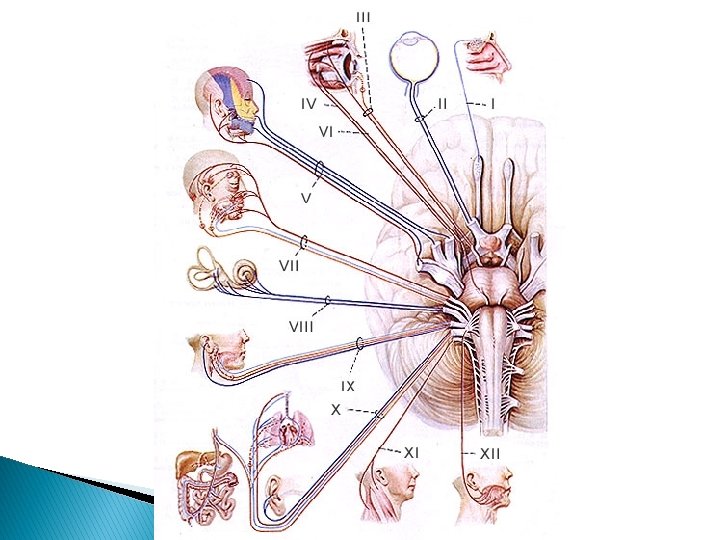

ÚTK: Heilataugar I. II. III. Olfactory: Teg: skyntaug - Virkni: lykt Uppruni eða endastöð: ventral hluta heilahvelanna Optic: Teg: skyntaug - Virkni: sjón – U/E: thalamus Oculomotor: Teg: hreyfitaug – Virkni: augnhreyfingar – U/E: miðheili

ÚTK: Heilataugar IV. V. Trochlear: Teg: hreyfitaug - Virkni: augnhreyfingar – U/E: miðheili Trigeminal: Teg: hreyfitaug/skyntaug – Virkni: tyggihreyfing kjálka / tilfinning andlits og tungu – U/E: miðheili og brú / mænukylfa

ÚTK: Heilataugar VI. VIII. Abducens: Teg: hreyfitaug – Virkni: augnhreyfingar – U/E: mænukylfa Facial: Teg: skyntaug/hreyfitaug – Virkni: bragð / hreyfingar andlits – U/E: mænukylfa Auditory vestibular: Teg: skyntaug – Virkni: heyrn, jafnvægi – U/E: mænukylfa

ÚTK: Heilataugar IX. Glossopharyngeal: Teg: skyntaug/hreyfitaug – Virkni: bragð / hreyfingar tungu koks - U/E: mænukylfa Vagus: Teg: skyntaug/hreyfitaug – Virkni: næmi og hreyfingar hjarta, lunga, maga og þarma – U/E: mænukylfa

ÚTK: Heilataugar XI. XII. Spinal accessory: Teg: hreyfitaug – Virkni: hálshreyfingar – U/E: mænukylfa Hypoglossal: Teg: hreyfitaug – Virkni: hreyfingar tungu – U/E: mænukylfa